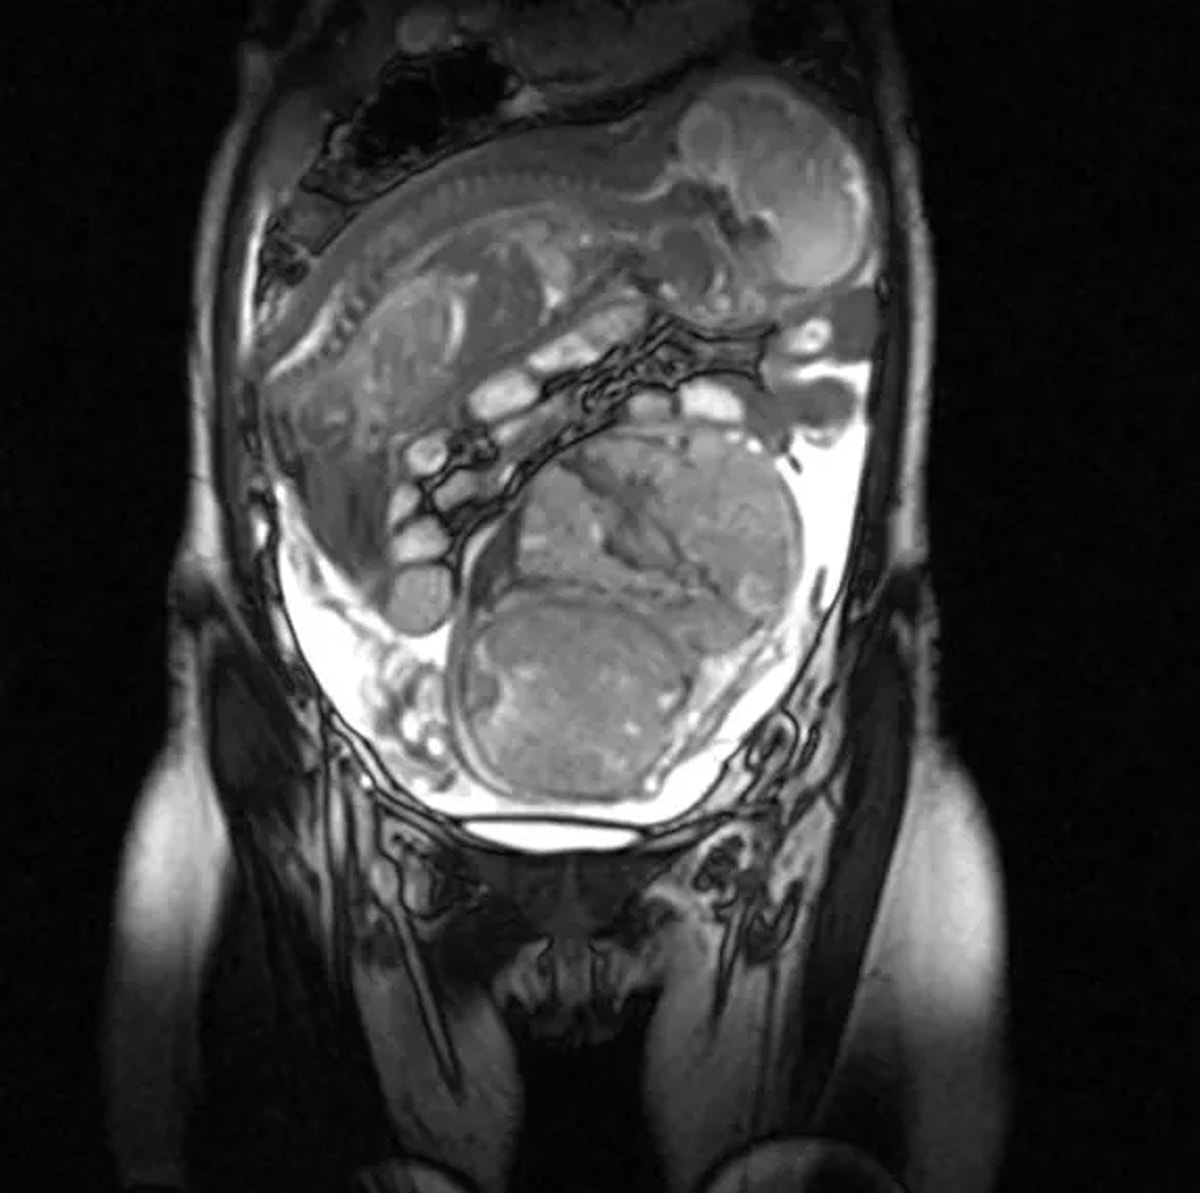

Брюшная Беременность Фото

Брюшная Беременность Фото 113 фото